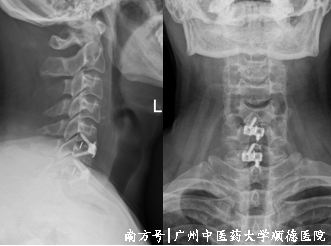

于是冯学烽主任为其行显微镜微创下颈椎手术,手术2个小时顺利完成,做完当晚黄先生说:“这四个月我终于睡了一个安稳觉,脖子也不用歪着了,左胳膊也不疼了。”

↑ C5/6、C6/7术后复查,颈椎曲度改善。